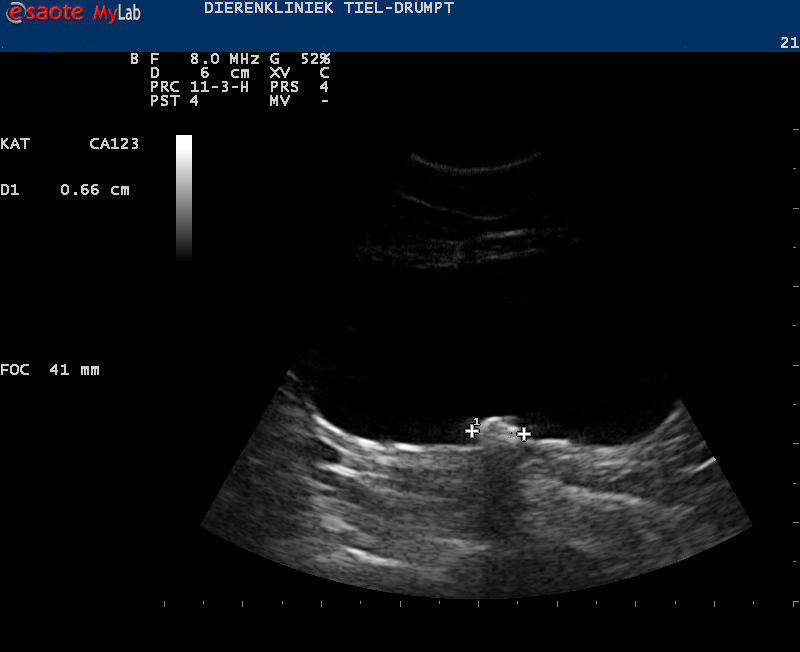

Het eerste dat moet gebeuren bij de behandeling is zorgen dat de urine uit de blaas kan, zodat de kat zijn gifstoffen kwijt kan. Hierbij, of direct hierna proberen we de oorzaak vast te stellen. Dit om te voorkomen dat er lang behandeld wordt zonder een goede kans op genezing.

De kater wordt in slaap gebracht, waarna er geprobeerd wordt om de plasbuis in de penis vrij te krijgen. In de meeste gevallen gaat het om een ontstekingsplug of gruis en in deze gevallen zal er een urinekatheter ingebracht worden. Deze wordt vastgehecht en moet een aantal dagen blijven zitten. De katheter zorgt voor een continue mogelijkheid tot het afvoeren van de urine, waarbij tevens de blaaswand rust krijgt. Na een aantal dagen spoelen en behandelen met medicatie halen we de urinekatheter eruit en zal er gecontroleerd moeten worden of de klachten niet terugkomen.